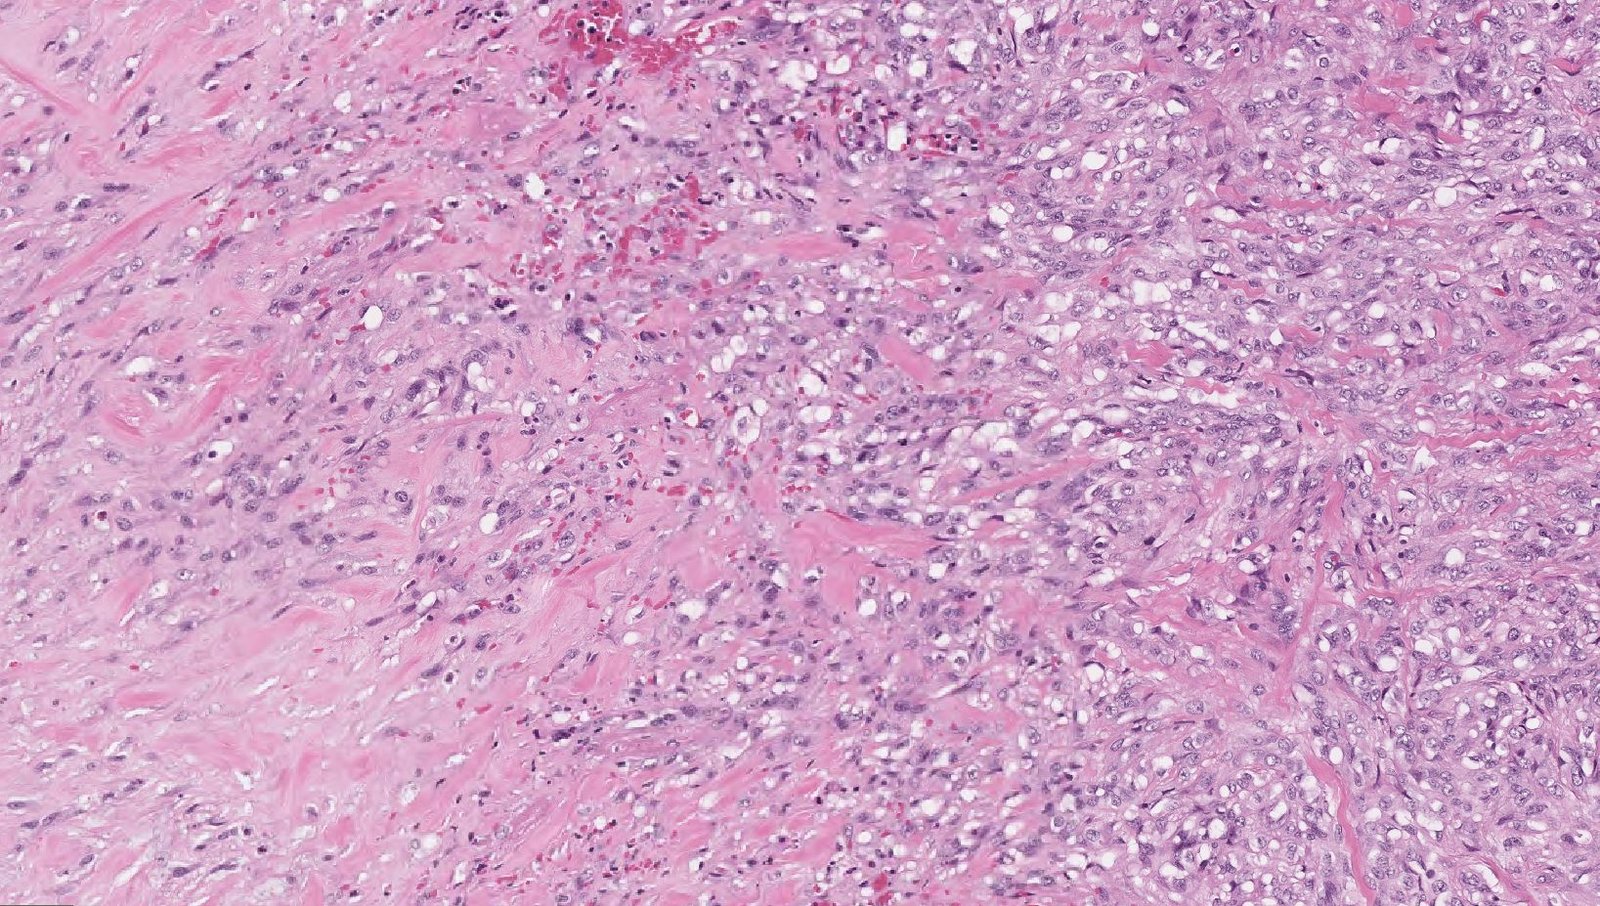

Case: ArmLesion

Final Diagnosis: